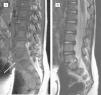

Se realizó radiografía simple en el momento del diagnóstico a 17 de los niños y resultó patológica en 15 (88%), con disminución del espacio discal en 13. También en ese momento, la gammagrafía, realizada en 6 casos, fue siempre positiva, al igual que la TC (4 casos). A todos los pacientes se les realizó RM al inicio (con un retraso respecto a la radiografía inicial de 1 a 7 días) y fue diagnóstica en el 100% de los casos, ya que mostró disminución o desaparición del espacio discal en todos los pacientes (ver fig. 2). Las tablas 3 y 4 recogen los datos obtenidos en la radiografía simple y la RM realizadas en el momento del diagnóstico, y la comparación de éstas con el siguiente control. De los 5 casos en que se vieron afectadas las raíces nerviosas, sólo 2 se acompañaron de clínica radicular: un caso de hipotonía en glúteos y extremidades inferiores (compresión de L5) y otro con reflejos osteotendinosos abolidos y Lassegue bilateral positivo (herniación discal con compresión de L4).

RM al diagnóstico. Espondilodiscitis L5-S1 con masa de partes blandas perivertebral. A: Sagital T1. B: Sagital T2. Aumento de partes blandas perivertebral indicativo de colección-absceso, por delante del cuerpo vertebral y hacia el canal espinal lateral (flecha). Espacio intervertebral disminuido, erosión y cambio de señal de los platillos vertebrales colindantes (inferior de L5 y superior de S1) y afectación discal.